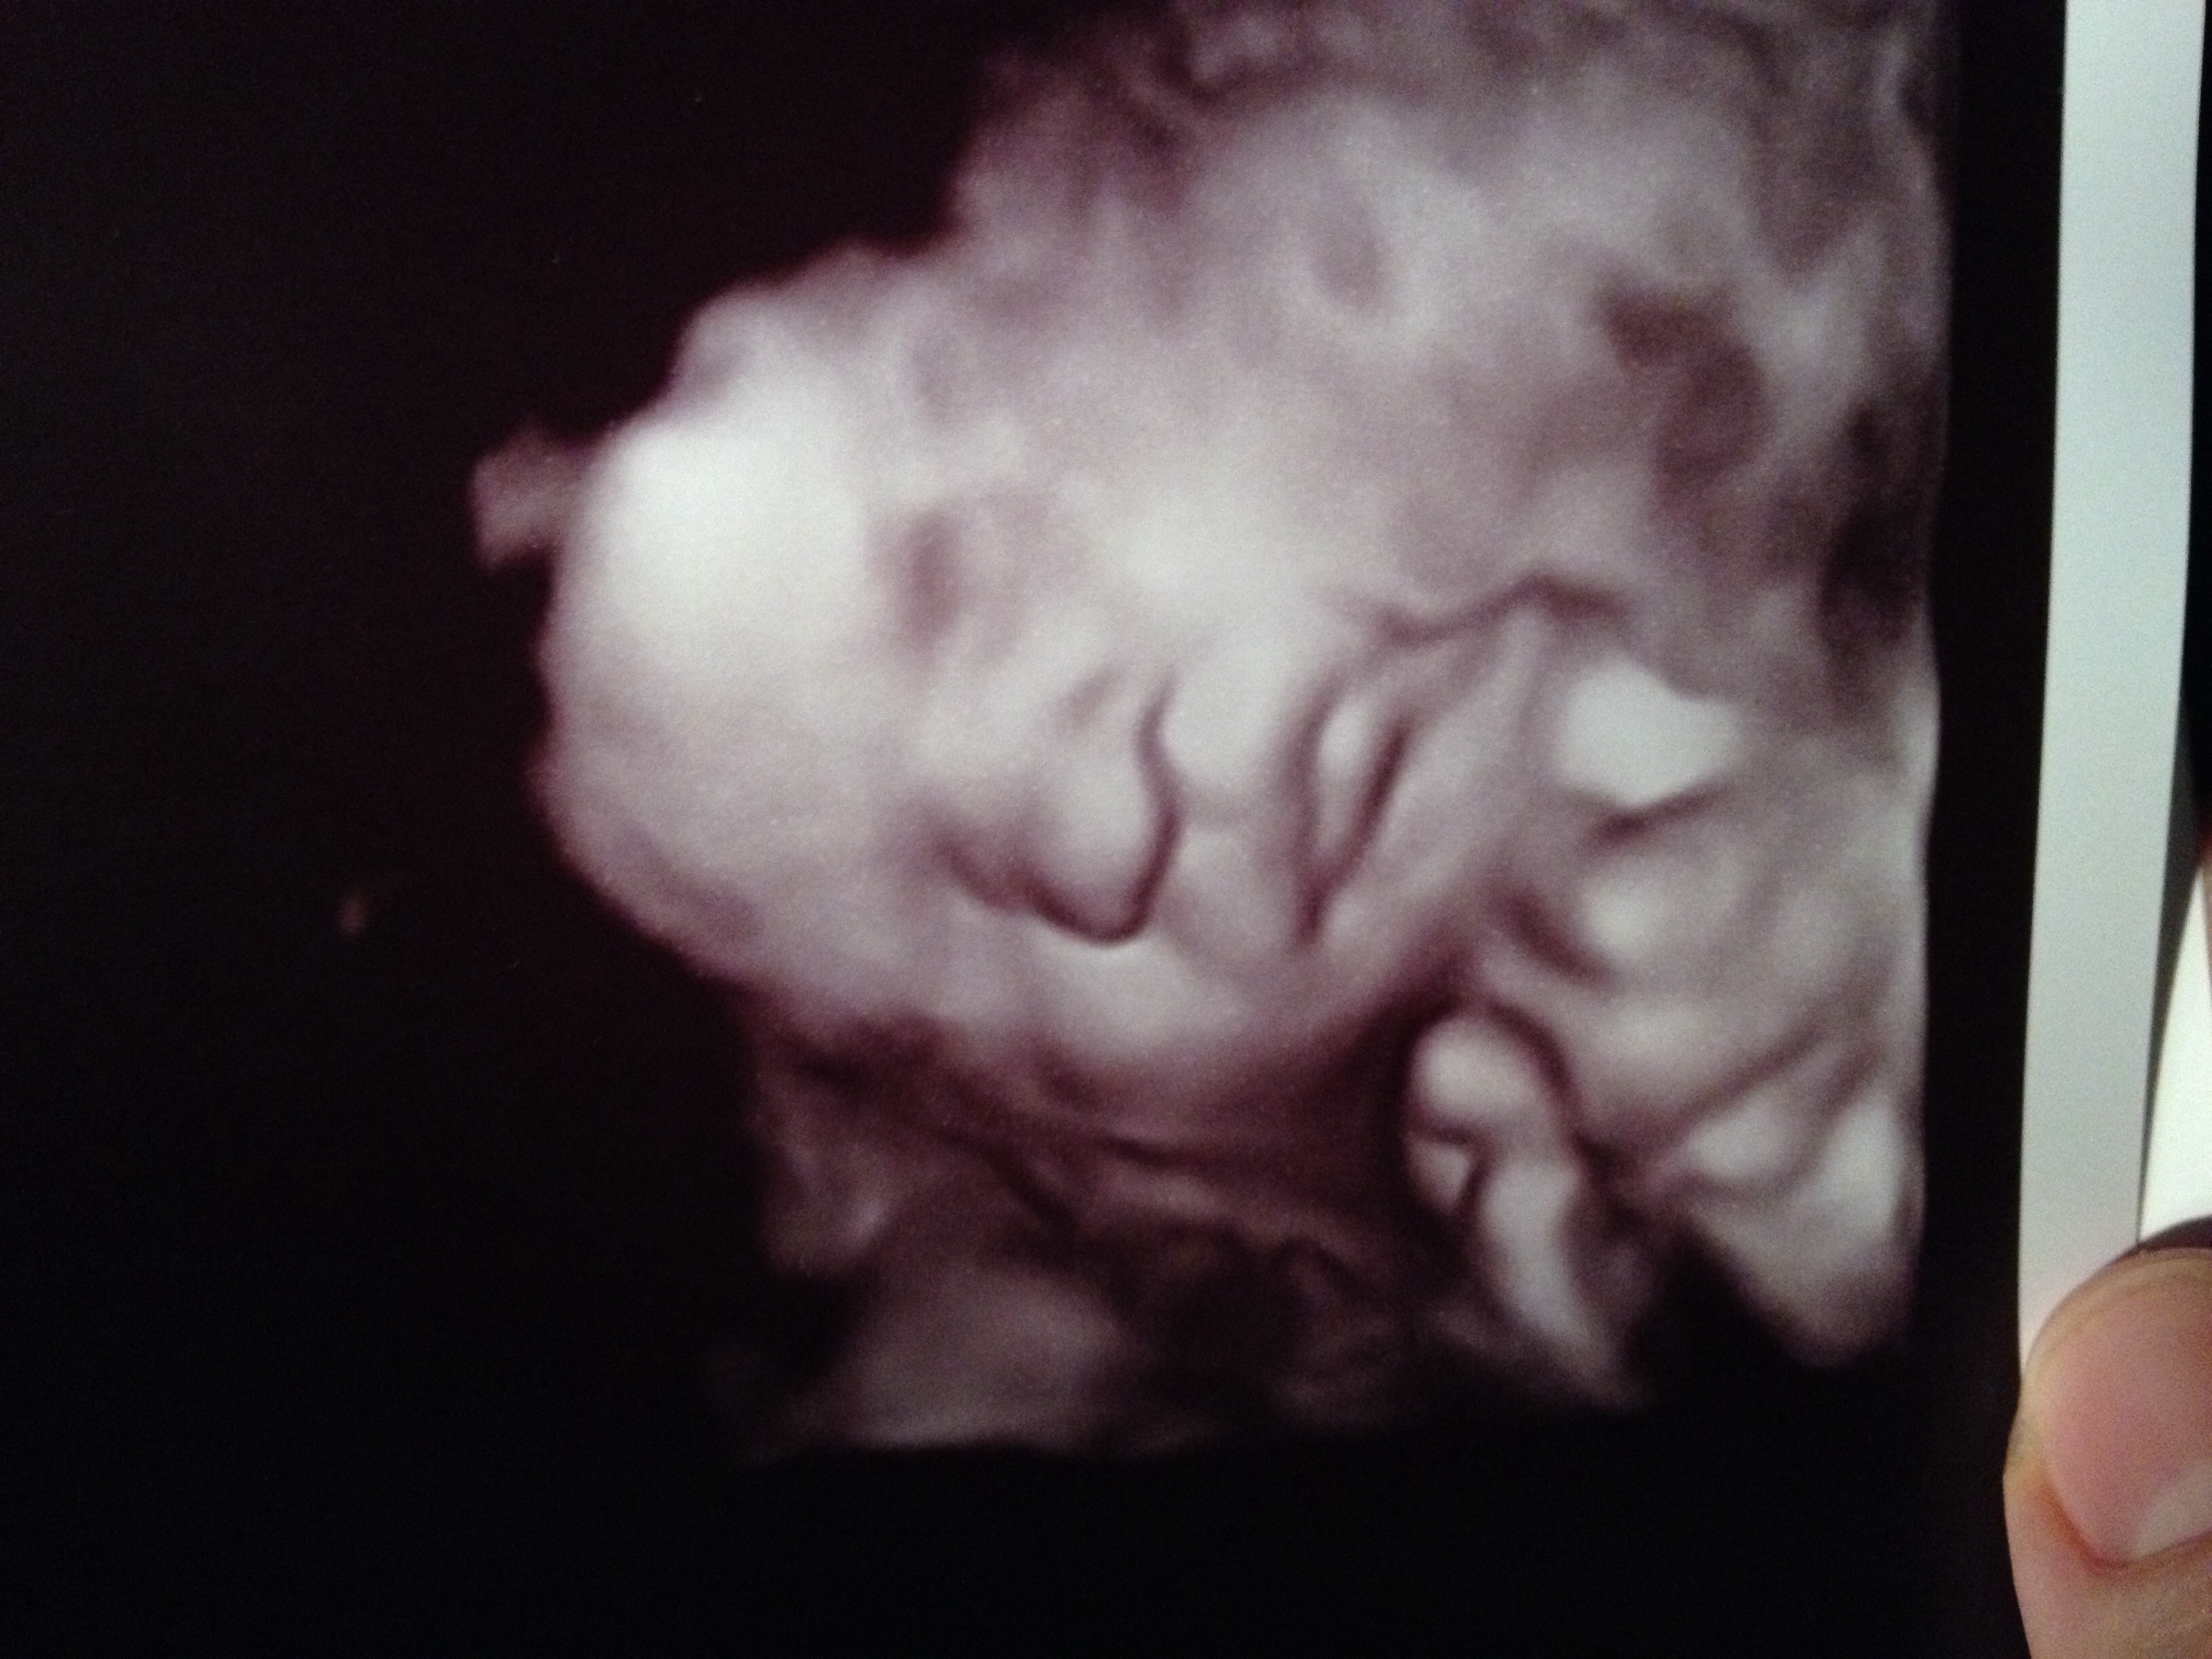

30.1 wks